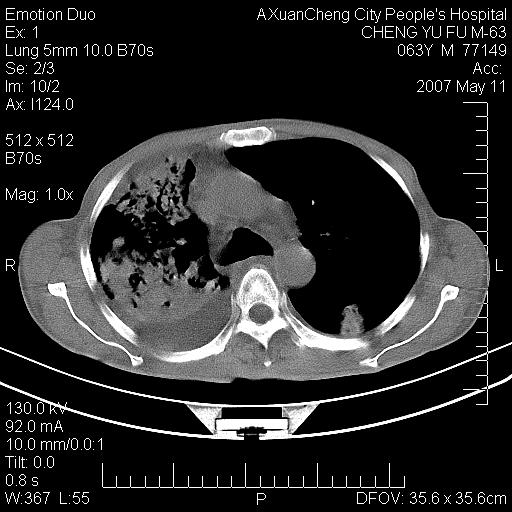

以下是引用小初学者在2007-5-11 19:32:00的发言:[br]1、首先考虑干酪性肺炎支气管播散[br]2、支气管肺泡癌待排

以下是引用zhangzhongshou在2007-5-11 19:30:00的发言:[br]细支气管肺泡癌可能性大。